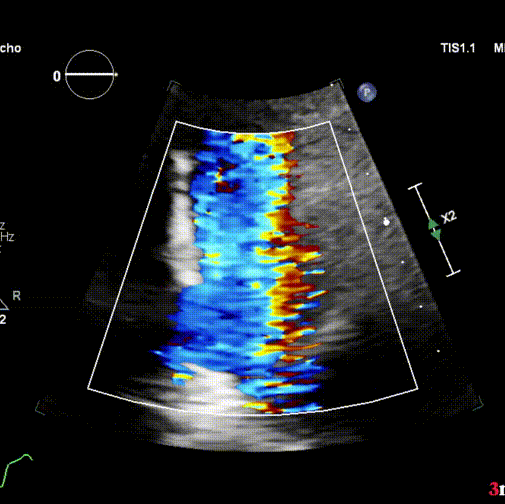

患者是一名21岁青年男性,既往行法洛氏四联症外科跨瓣补片修复术,患有重度肺动脉瓣反流且有显著的右心室、肺动脉扩张及左心室功能障碍。介入手术采用局部麻醉方式,患者清醒状态下穿刺右侧股静脉作为主入路,术中进行了造影及球囊测量,经中美2个团队的再次在线讨论,结合术前CT分析结果,最终精准的选用P34-25(瓣膜腰部直径34mm,长度25mm) VenusP-Valve瓣膜完成植入,即刻造影和超声综合评估显示瓣膜植入位置完美,无反流及残余压差,左右肺动脉分支血流未受影响。术后Scott Lim教授与冯沅教授就手术过程再次进行了讨论,并分享了植入体会。次日好消息传来,超声检查示右室明显变小,无任何肺动脉瓣反流,左室功能恢复正常。术后患者恢复迅速,无并发症发生,患者于术后24小时内,当地时间6月18日出院。

瓣膜最终植入效果